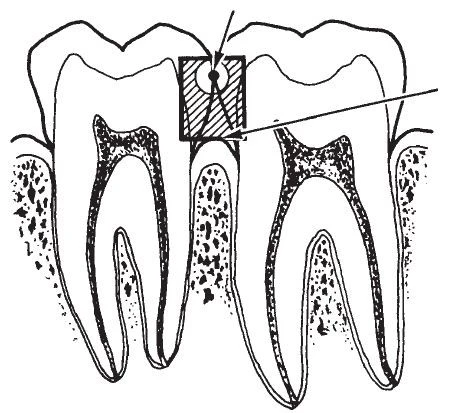

Hình 1. Quá trình mất khoáng ở mặt nhai và mặt bên đi từ men răng đến ngà răng và chạm vào tuỷ răng.

Tỉ lệ và mức độ mất khoáng tuỳ thuộc vào nhiều nhân tố. Mất khoáng xảy ra nhanh hơn ở những tổn thương đang hoạt động với sự hình thành những tinh thể trống. Mất khoáng có thể lan rộng vào phần ngà trước khi mặt ngoài răng sụp xuống, dẫn đến tạo thành một xoang có thể thấy được trên lâm sàng. Với tổn thương tiến triển và không can thiệp thì mất khoáng tiến triển xuyên qua men, ngà và thậm chí vào đến tuỷ răng và có thể làm hỏng răng.

Tổn thương sâu răng ở trẻ em và thanh thiếu niên hầu hết thường ở mặt nhai các răng sau. Quá trình mất khoáng hoá bắt nguồn từ men răng tại những hố rãnh – nơi mảng bám vi khuẩn tích tụ. Tổn thương lan rộng dọc theo trụ men và nếu như không có gì cản trở sẽ tiến vào đường nối men ngà, ở đây có thể thấy được một đường thấu quang mỏng giữa men răng và ngà răng.

Tổn thương măt nhai thường bắt đầu ở bờ thành của rãnh hơn là đáy rãnh và sau đó có khuynh hướng xuyên qua gần như vuông góc hướng về đường nối men – ngà. Những tổn thương sớm có hình ảnh trên lâm sàng như là phấn trắng, vàng, nâu hoặc đổi sang màu đen ở rãnh mặt nhai. Khi phát hiện những rãnh đổi màu với bề mặt nhai trên lâm sàng còn nguyên vẹn thì cần chụp X quang để xác định xem liệu một tổn thương sâu răng có vượt qua đường nối men ngà chưa. Nếu tổn thương không băng ngang qua đường nối men ngà thì có thể không thấy được trên X quang.